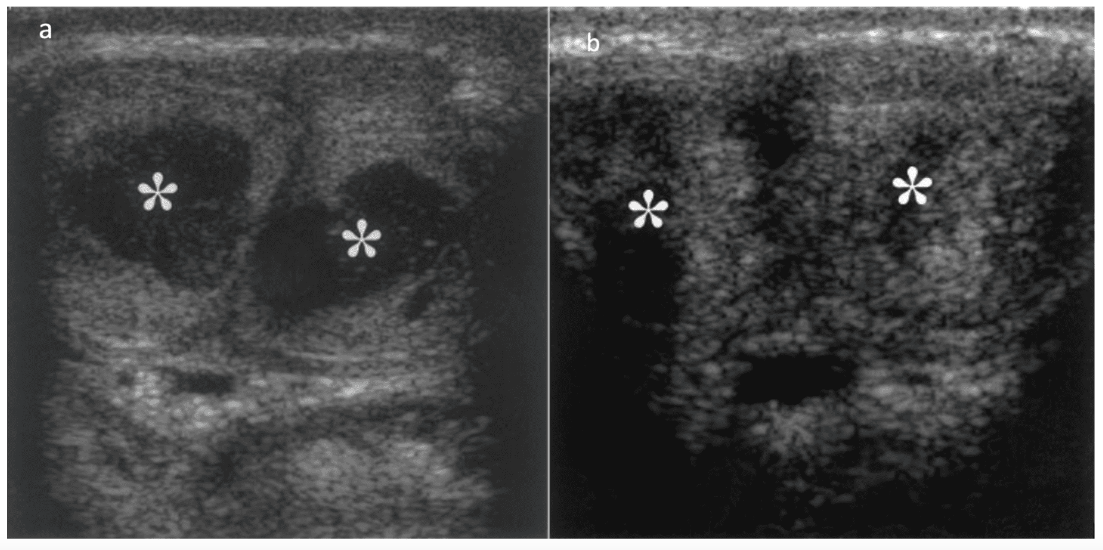

Vídeo de cirugía

Les presentamos un caso de un paciente masculino de 48 años, con antecedentes de tres días de priapismo tratado mediante derivación. Se le ofreció la colocación de un implante después de ocho meses de haber sufrido el episodio de priapismo. Durante el examen clínico se evidenció fibrosis extensa en ambos cuerpos cavernosos, afectando la totalidad del lado izquierdo y la mitad distal del lado derecho.

Primer tiempo: Se colocó un implante en la mitad del cuerpo cavernoso derecho, mientras que el izquierdo quedó sin intervenir.

Segundo tiempo: Procedimos con la colocación completa de la prótesis, lo cual se muestra en detalle en el video.